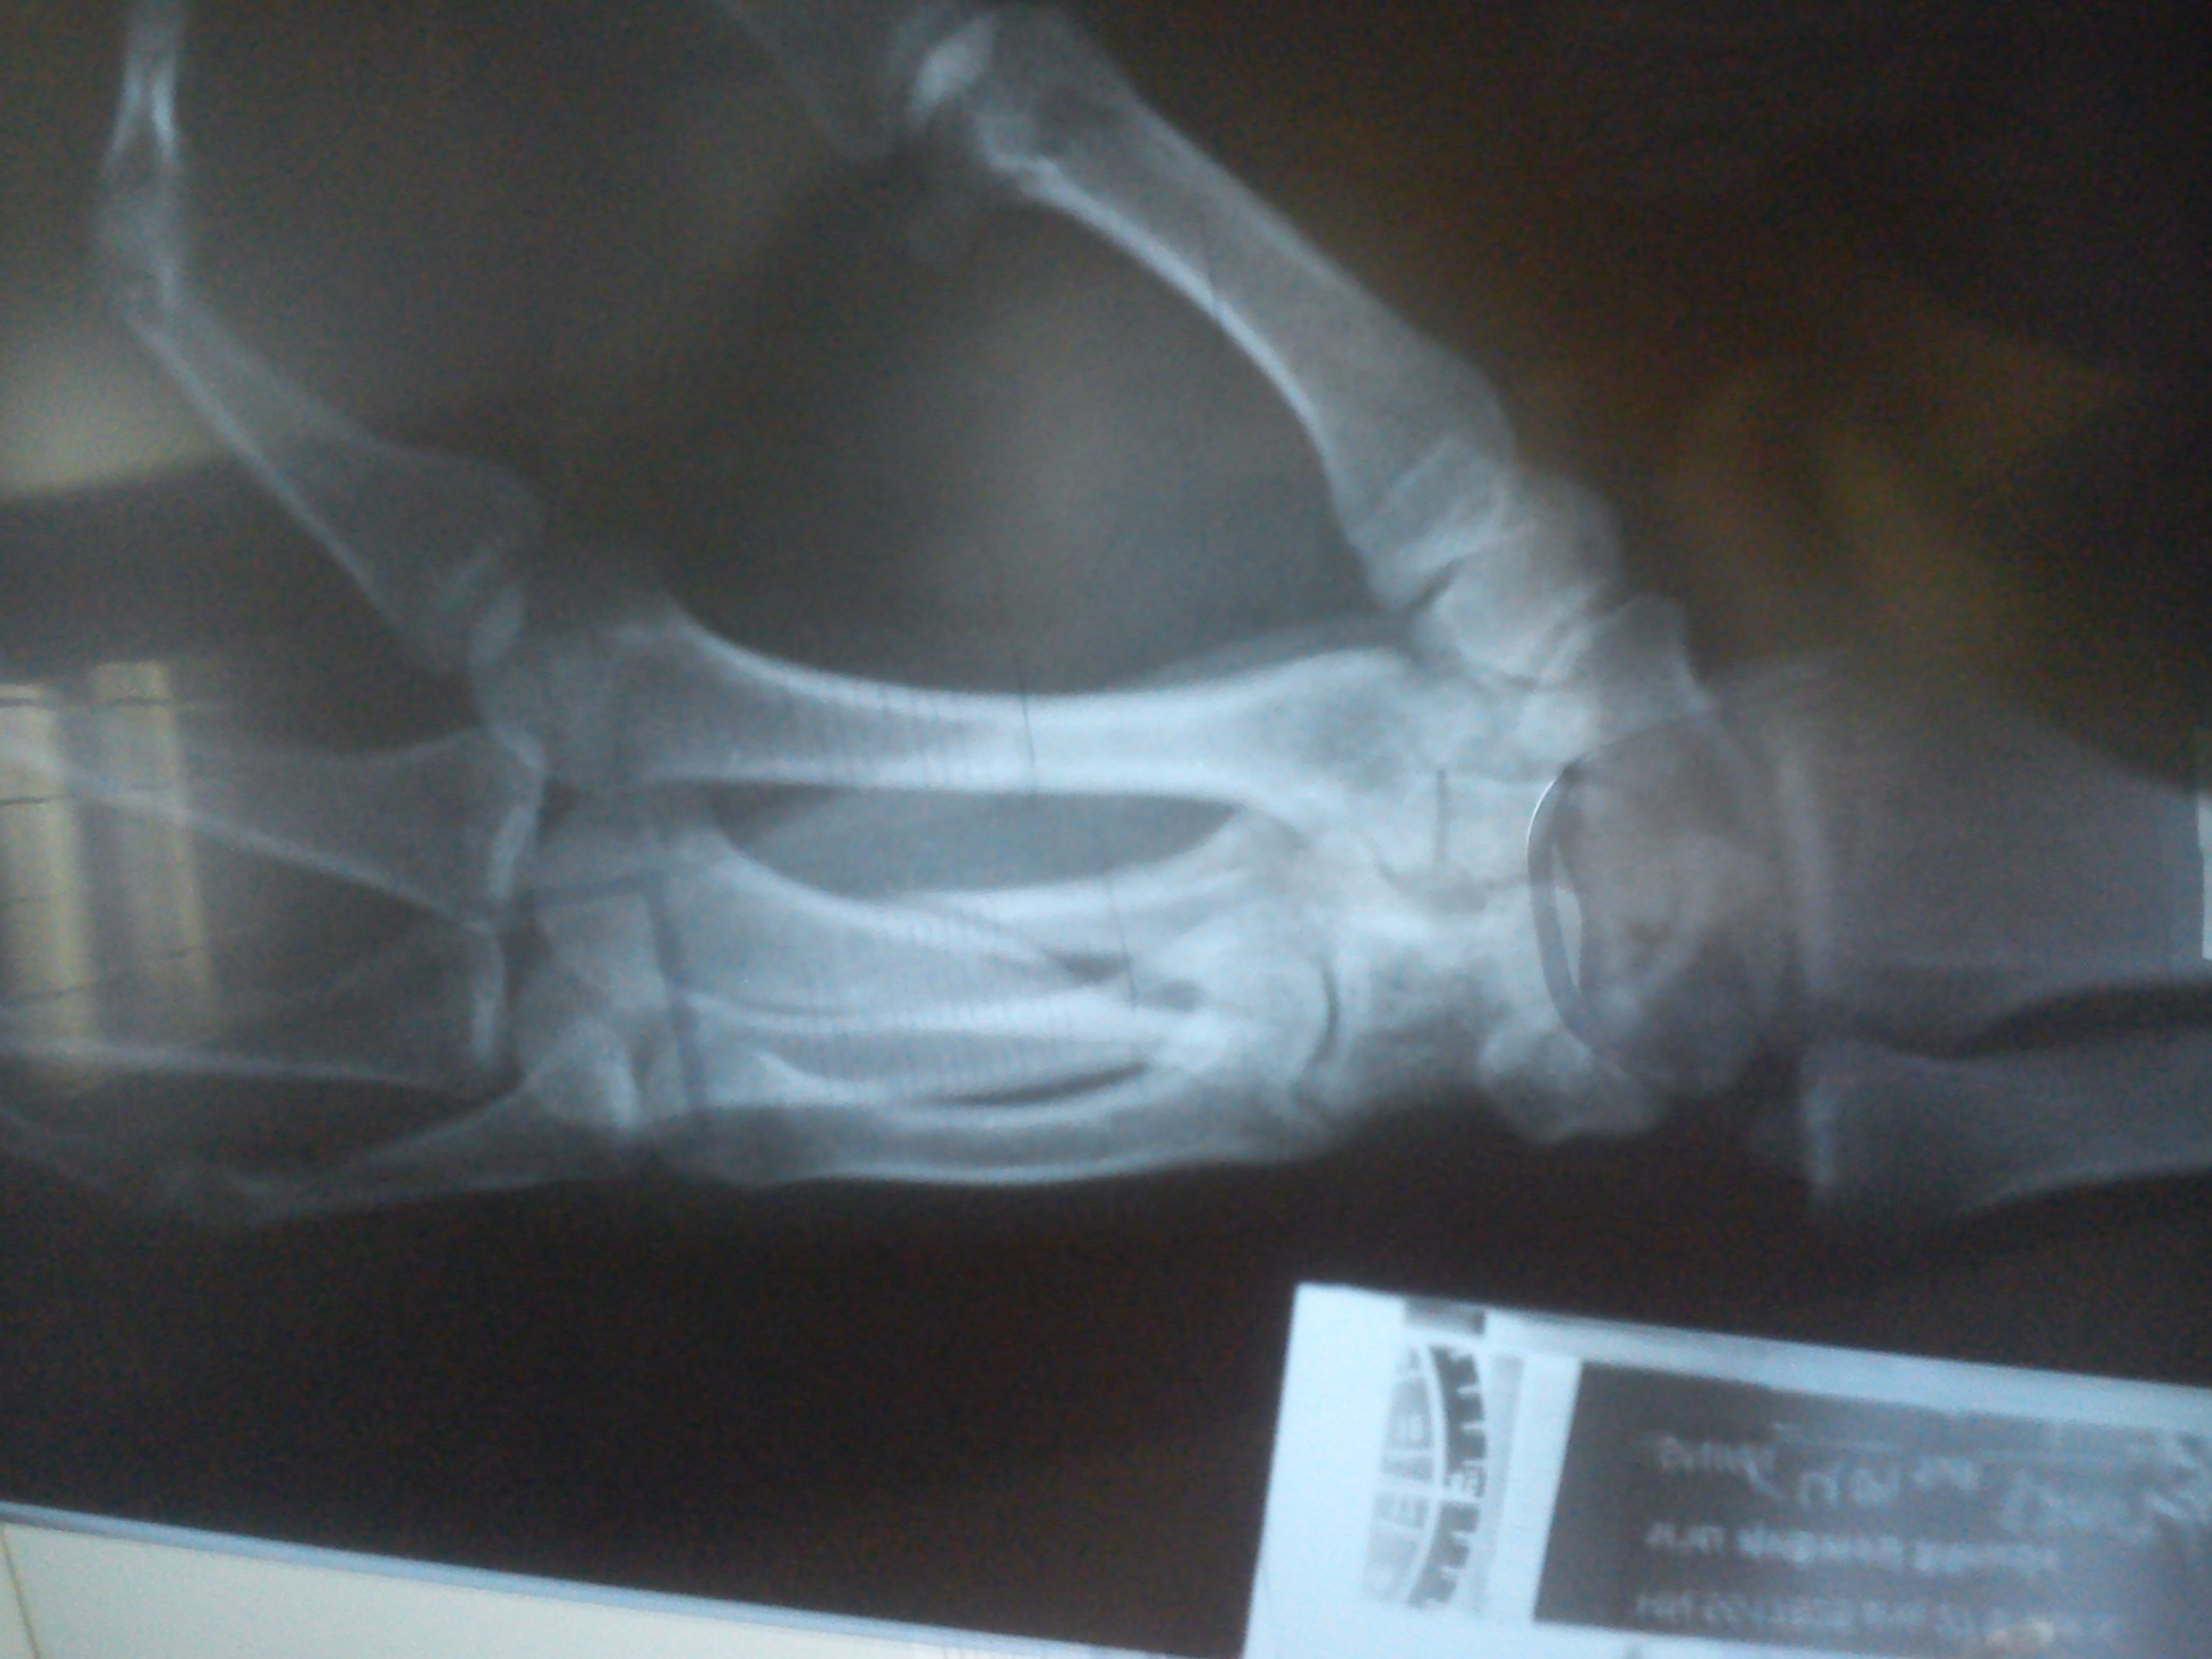

ปัญหา จะมี ๒ ประเด็นหลัก

๑. กระดูกนิ้ว สั้นลง

๒. กระดูกนิ้ว บิดหมุน

สิ่งที่จะตามมา ก็คือ กำมือไม่แน่น หรือ กำมือแล้วนิ้วจะซ้อนทับกัน ..

แต่การประเมินว่า ควรจะรักษาแบบไหน ก็ต้องอาศัยการตรวจร่างกาย และ ประเมินกิจกรรมการใช้งาน .. เช่น ถ้ามีอาชีพ นักเปียนโน .. แบบนี้ ก็ผ่าเลย เพราะ นิ้วสั้นลงไป ก็จะมีปัญหาในการเล่นเปียโน เป็นต้น

กระดูกมือหัก เชื่อมผิดรูป

เมื่อวานไปให้หมอที่โรงบาลเอกเรย์มา คุณหมอบอกว่ากระดูกมีรอยเชื่อมแล้ว

ก้อเลยให้เอาเฝือกออก ผมอยากรู้ว่ากระดูกมันเชื่อมผิดรุปแบบนี้ จะมีผลอะไรมั้ยคับ

คือตอนนี้ผมกำมือไม่สุดอ่ะคับ แล้วก็เสียวตรงกระดูกตลอดเลย